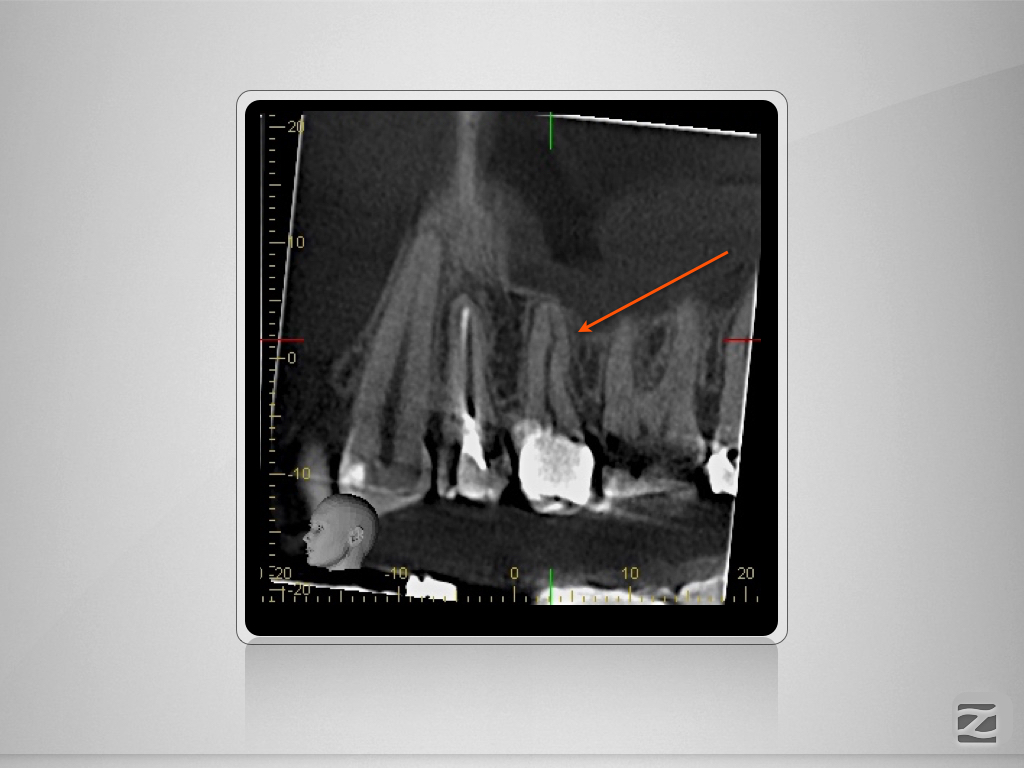

Therapieplanung in 3D